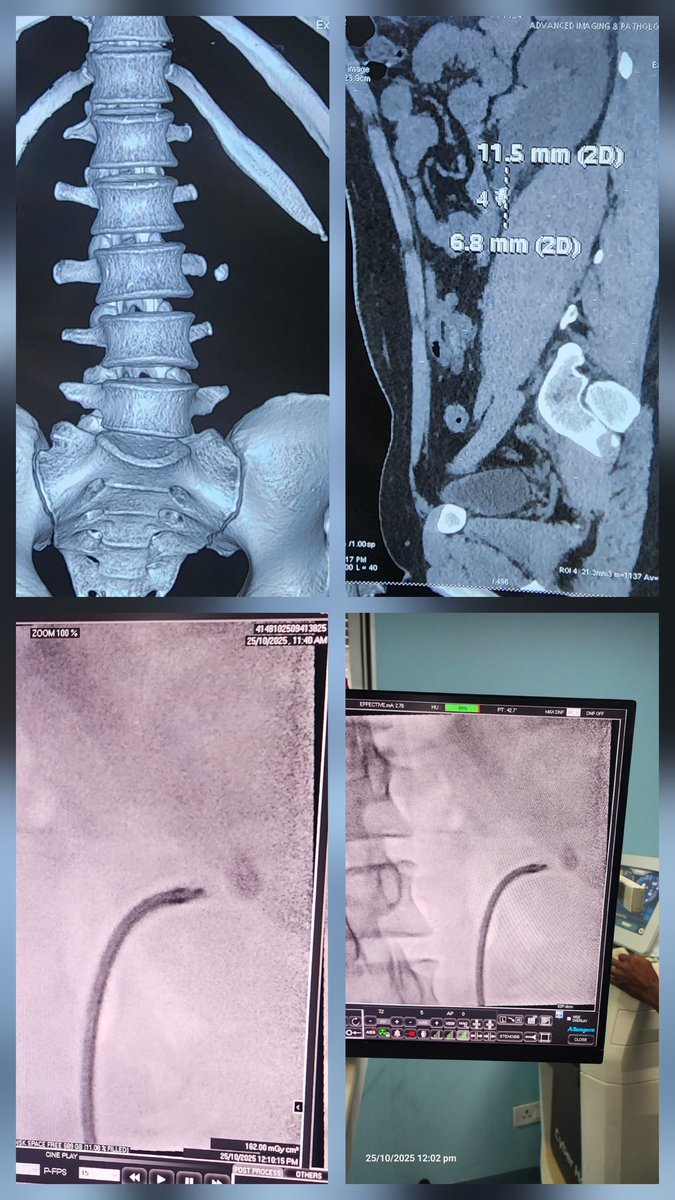

Suction assisted MiniPCNL. partial Staghorn LK Lower Calyx. 3D CT recon helps select ideal calyx entry for complete clearance. 25 min job. @endouro @endouroacademy @sbinhamrii @DocGauhar @amy_krambeck @DrParimalGharia @UroZedman @TFL_URO_APIS @Endo_Society